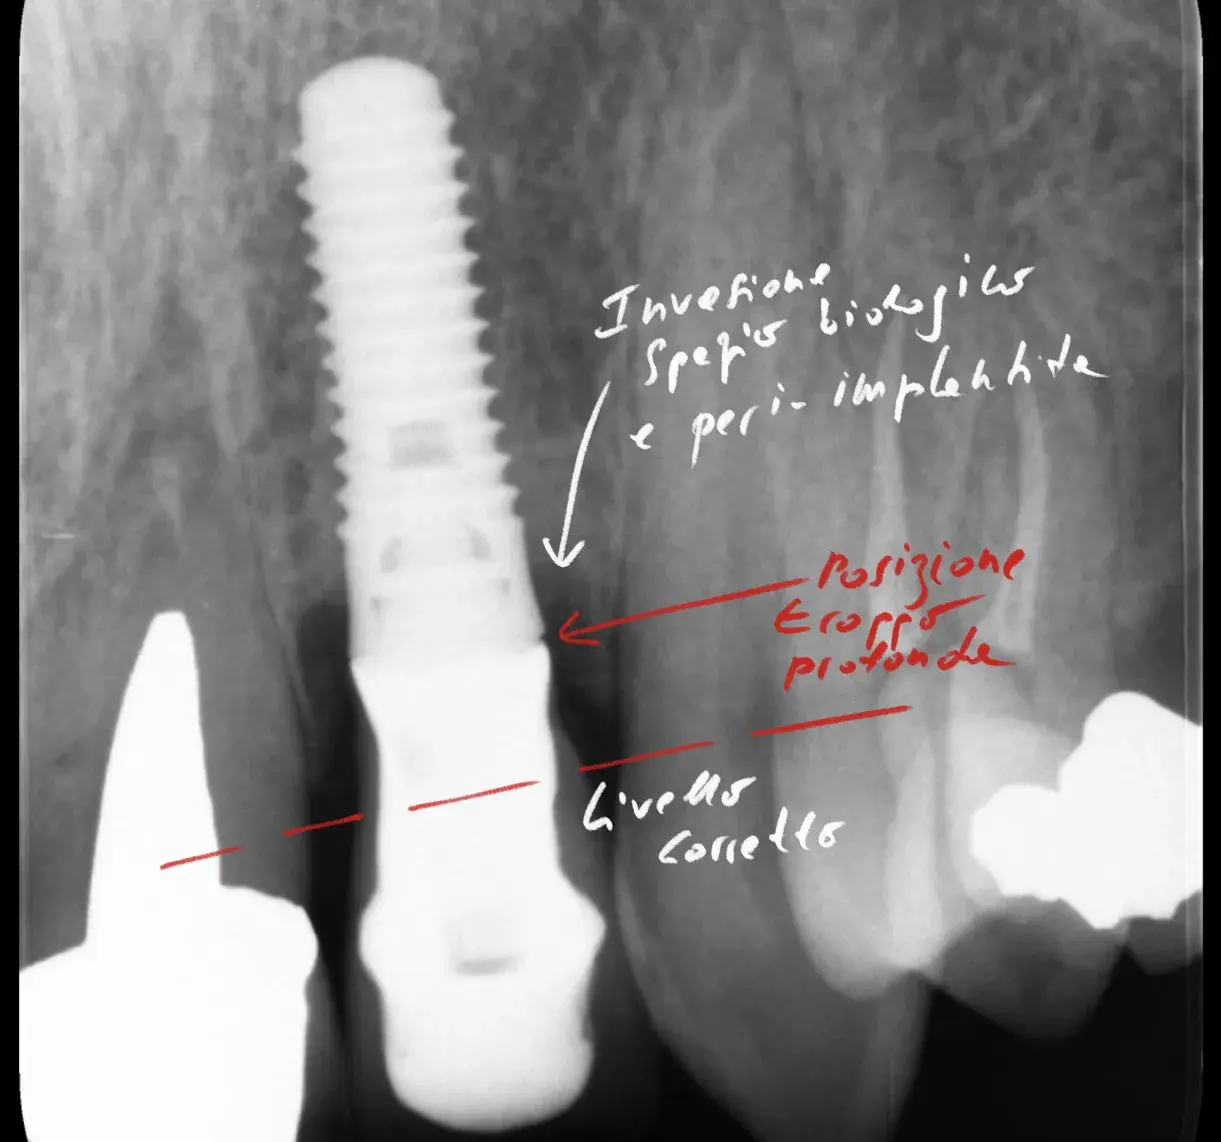

Bone-level, tissue-level, connessione conica: la profondità corretta cambia con il tipo di connessione. Perché sbagliarla causa riassorbimento osseo.

Un impianto mal posizionato causa perdita ossea di 0,25 mm ogni 10° di errore. Come riconoscere il problema, quando si può correggere e quando va rimosso.

Negli ultimi decenni si è enfatizzato il rischio di peri-implantite negli impianti a superficie ruvida, ma non tutti ne sono affetti. Problemi come erra...